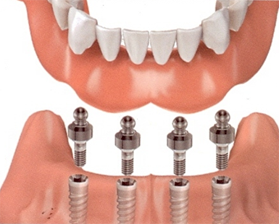

img3 img4

Implant supported overdenture Implant supported bridge

3. For all missing teeth: it could be an removable overdenture or fixed bridge.

2. Overdenture implants, used to support dentures.

3. Implant supported full mouth rehabilitation